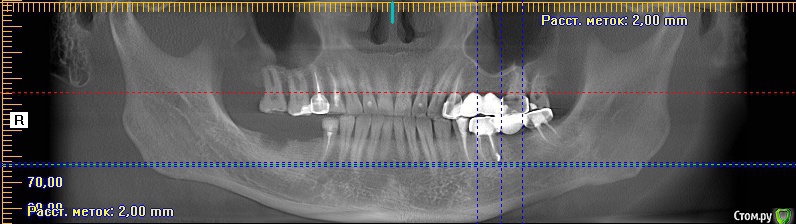

meld Опубликовано 7 ноября, 2017 Поделиться Опубликовано 7 ноября, 2017 Здравствуйте! Чуть больше года назад заболел 36 зуб. Я его пролечил с диагнозом периодонтит. 37 зуба нет. Было принято решение поставить мост с опорой на 36 и 38 зубы. 38 зуб был депульпирован в январе 2017 г. В мае 2017 я поставил мост. Вчера 38 зуб стал болеть при жевании. Боль не сильная, ломящая, через некоторое время проходит. Сегодня съездил в клинику, где лечил зубы, на осмотр. Осмотр ничего не выявил. Сделали прицельный снимок - по словам врачей (а их было двое) криминала тоже нет. Показал им свою томограмму - там тоже (по их словам) ничего нет. Посмотрите, пожалуйста, что не так. СпасибоСрезы 36 зуба Ссылка на комментарий

IvanK Опубликовано 7 ноября, 2017 Поделиться Опубликовано 7 ноября, 2017 ЗдравствуйтеЕсть периапикальные измененияя за удаление и последующую имплантацию 1 Ссылка на комментарий

meld Опубликовано 10 ноября, 2017 Автор Поделиться Опубликовано 10 ноября, 2017 Был позавчера-вчера у терапевта в клинике, где имплантируюсь. Пролечил один зуб с кариесом, почистил зубы. Терапевт оба зуба (38,36) приговорил на выход. Сказал, что 38 можно перелечить, но без гарантии, а в 36 есть разрежение костной ткани, но перелечить его уже нельзя. Как я сейчас понимаю (и терапевт это подтвердил) этот зуб мне в прошлом году неправильно пролечили. Мне его лечили около недели, а терапевт сказал, что лечит подобные зубы не менее 3 месяцев. Рекомендация терапевта - оставить все как есть с рентген контролем раз в 3-6 месяцев, пока не заболит, либо пока не увеличится кисты. Когда импланты справа появятся, тогда и можно будет суетиться по поводу левой стороны. Пожалуйста, не закрывайте тему, может быть еще вопросы появятся. Спасибо всем за внимание. Ссылка на комментарий

IvanK Опубликовано 10 ноября, 2017 Поделиться Опубликовано 10 ноября, 2017 если хотите сохранить 36 - необходимо повторное эндодонтическое лечение, ищите Врача или удаляйте и 2 имплантата - 36 и 37 Ссылка на комментарий